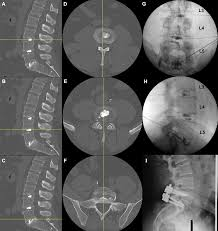

In a discogram, a contrast liquid is injected into the center of one or more spinal discs using x-ray guidance. This injection may temporarily reproduce the patient's back pain symptoms. As part of the procedure, an x-ray or CT scan also may be performed to obtain pictures of the injected disc. - How should I prepare?

- Discography uses imaging guidance to direct an injection of contrast material into the center of one or more spinal discs to help identify the source of back pain. It also is used to help guide the treatment of abnormal intervertebral discs – sponge-like cushions located between the vertebrae of the spine.

Your doctor will use an imaging technique (fluoroscopy) that enables him or her to watch as the needle enters your body. Fluoroscopy allows more precise and safer placement of the needle into the center of the disk to be examined. A contrast dye is then injected into the disk, and an X-ray or CT scan is taken to see if the dye spreads.

- Your doctor will review the images and the information you provided about the pain you experienced during the procedure. Both are important to help pinpoint the source of your back pain. Your doctor will use this information to guide your ongoing treatment or prepare for surgery.